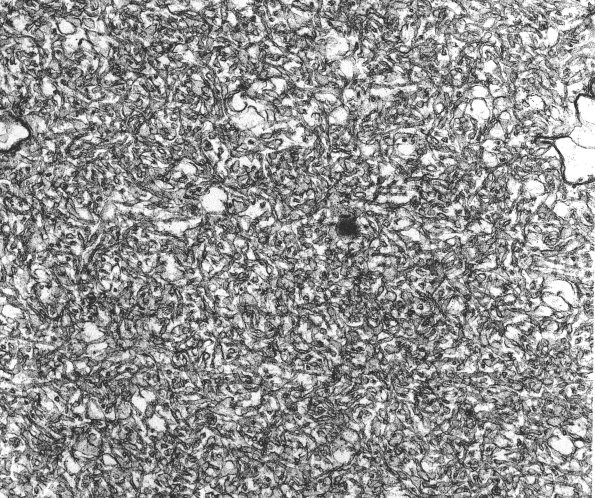

Washington University Experience | PERIPHERAL NEUROPATHY | 5 AXONAL REGENERATION | 2A8 Growth cone, rat frustrated regeneration 40,000X

Delicate tubulovesicular material is characteristic of enlarged growth cones. (electron micrograph)